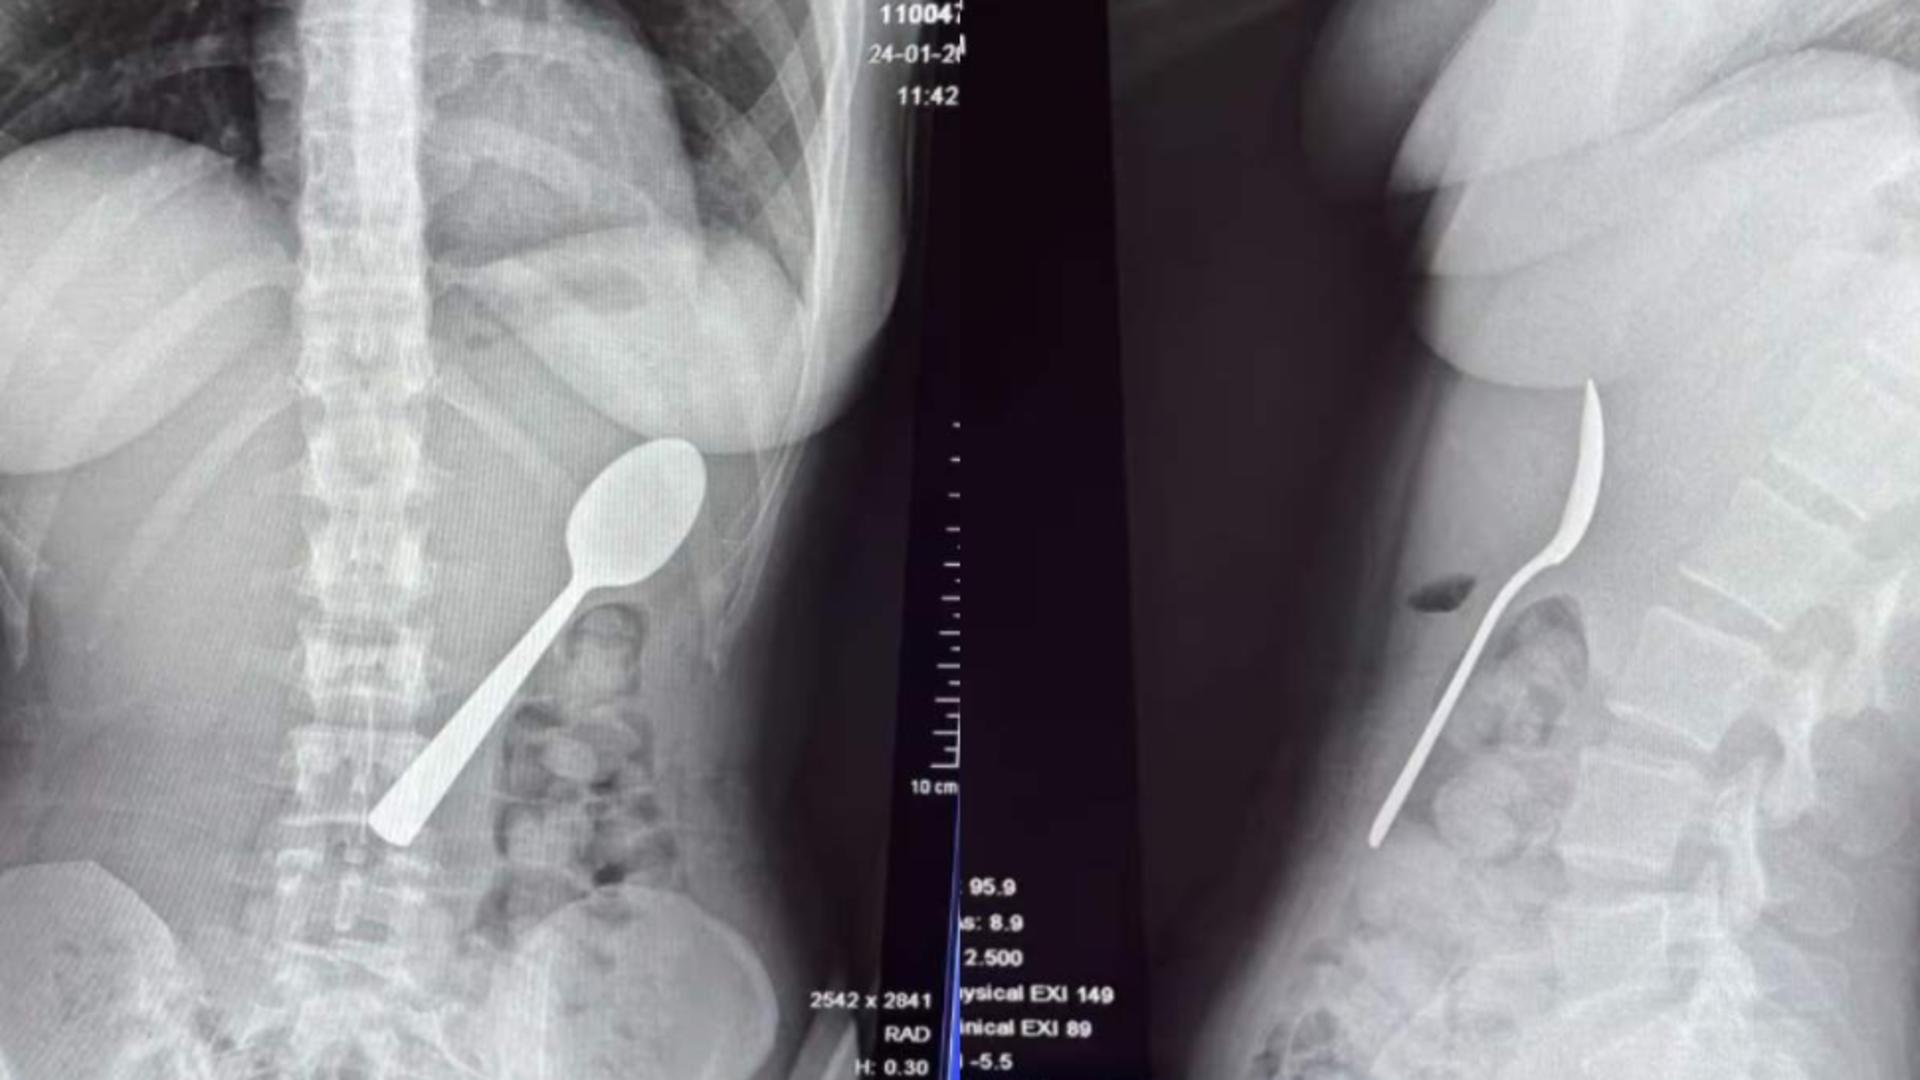

Reymy Amelinckx a povestit că stătea pe canapea și mânca iaurt, ținând lingura în gură pentru a avea mâinile libere să răspundă la un mesaj. Câinele său, un vizsla maghiar pe nume Marley, a sărit peste ea, iar surpriza a făcut ca lingura să alunece în gât. „Am fost atât de surprinsă încât mi-am dat capul pe spate și, înainte să realizez ce se întâmplă, lingura era deja în stomac. A trebuit să aleg între a mă sufoca sau a o înghiți”, a explicat tânăra.

Inițial, ea a încercat să scoată lingura cu mâna, dar situația s-a dovedit prea rapidă și periculoasă. Abia după câteva ore și după ce simptomele: balonare, grețuri și dificultăți la masă, au persistat, tânăra a decis să meargă la spital.

Două zile mai târziu, lingura a fost îndepărtată sub anestezie locală, fără a fi necesară o intervenție chirurgicală deschisă. Procedura a implicat rotirea lingurii în stomac, ceea ce a cauzat o mică hemoragie gastrică, însă tânăra a declarat că s-a simțit imediat ușurată după finalizarea procedurii.